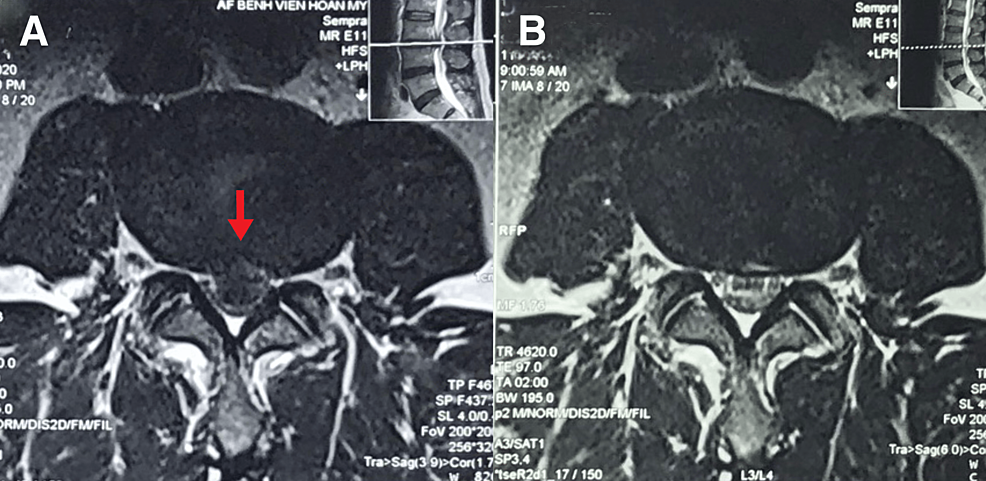

近期,香港與越南的脊醫聯合發表了一個驚人的病例報告(1)。報告中描述了一位52歲的亞洲男性,他因急性L3/L4椎間盤突出而經歷了嚴重的腰背痛和雙側神經根病變,導致嚴重的脊髓管狹窄和雙側L4神經根壓迫,造成嚴重的下背痛與雙腿神經痛。MRI影像顯示了巨大的中央型突出。這位患者選擇了為期十週的保守治療計劃,其中包括高速低振幅的脊椎手法矯正、輔助療法和家庭運動。

令人驚訝的是,即使患者初始狀況極差,在治療過程中,患者有了顯著的疼痛緩解、功能改善和近乎恢復的症狀。六個月後的隨訪MRI顯示L3/L4椎間盤突出消失,並且九個月後患者仍然無症狀。這個案例引起了對於腰椎椎間盤突出自癒潛力和保守治療的重要性的關注。